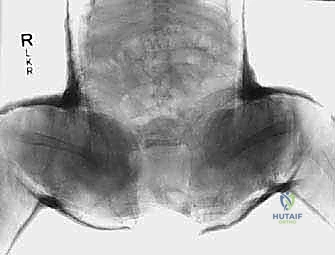

2. الأشعة السينية (X-Rays)

عندما يبلغ الطفل 6 أشهر فما فوق، تبدأ مراكز التعظم في الظهور في رأس الفخذ. في هذه المرحلة، تصبح الأشعة السينية ضرورية وأكثر دقة من الموجات فوق الصوتية.

يقوم الأستاذ الدكتور محمد هطيف بتحليل دقيق للأشعة السينية، حيث يرسم خطوطاً وهمية (مثل خط هيلجينراينر وخط بيركين) لتحديد موقع رأس الفخذ بدقة، وقياس "مؤشر الحُق" (Acetabular Index) لمعرفة مدى ضحالة التجويف. هذه القياسات حاسمة لتحديد ما إذا كان الطفل يحتاج إلى جراحة أم لا.

الرد المغلق والجبس البنطلوني (Closed Reduction and Spica Cast):

- العمر المناسب: من 6 أشهر إلى 18 شهراً (أو إذا فشل حزام بافليك).

- الآلية: يتم إجراؤه في غرفة العمليات تحت التخدير العام. يقوم الدكتور هطيف برد مفصل الورك يدوياً (بدون شق جراحي) بلطف شديد لضمان عدم إلحاق الضرر بالأوعية الدموية المغذية لرأس الفخذ. بعد التأكد من استقرار المفصل (غالباً باستخدام صبغة مفصلية Arthrogram)، يتم وضع الطفل في "جبس بنطلوني" (Spica Cast) يغطي الخصر والساقين لتثبيت الورك في مكانه لمدة تتراوح بين 3 إلى 6 أشهر (مع تغيير الجبس كل فترة).